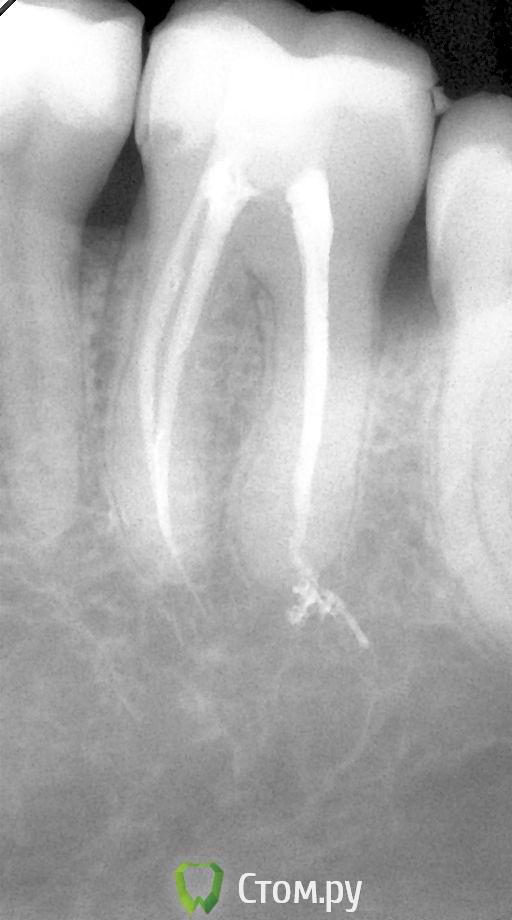

Каплан Опубликовано 25 ноября, 2011 Поделиться Опубликовано 25 ноября, 2011 не путайте. ЭДТА может быть разной концентрации. Одна, в составе таких препаратов как RC-prep, применяется для расширения каналов. Другая (кажется, 17%) применяется при финишной обработке канала для удаления смазанного слоя. Ее-то и заменяют лимонкойRC-Prep - это 15% гель ЭДТА. как бы 2 процента тут погоду думаю не сильно меняют, вопрос в "форме" - жидтким мыть легче... Насчет того сколько отступать - зависит от системы, и формы канала. нет одного рецепта...Как пример, померил по ап.лок, отнял 1 мм, и до 30.06 М2, потом еще раз померил, и на выходе получил упор не на 1 мм меньше, а на 0,5 мм, чем изначально. А планировал 0,5 мм ручками доработать под контролем ап.лок. пришлось финишировать на этой длине 35.02. http://s017.radikal.ru/i424/1111/8b/2c06a0a1f25et.jpgесть исследования по изменению рабочей длины для некоторых эндо-систем.. (для протейперов и профайлов точно есть. еще кажется К3). там вообще оч интересные циферки... Ссылка на комментарий